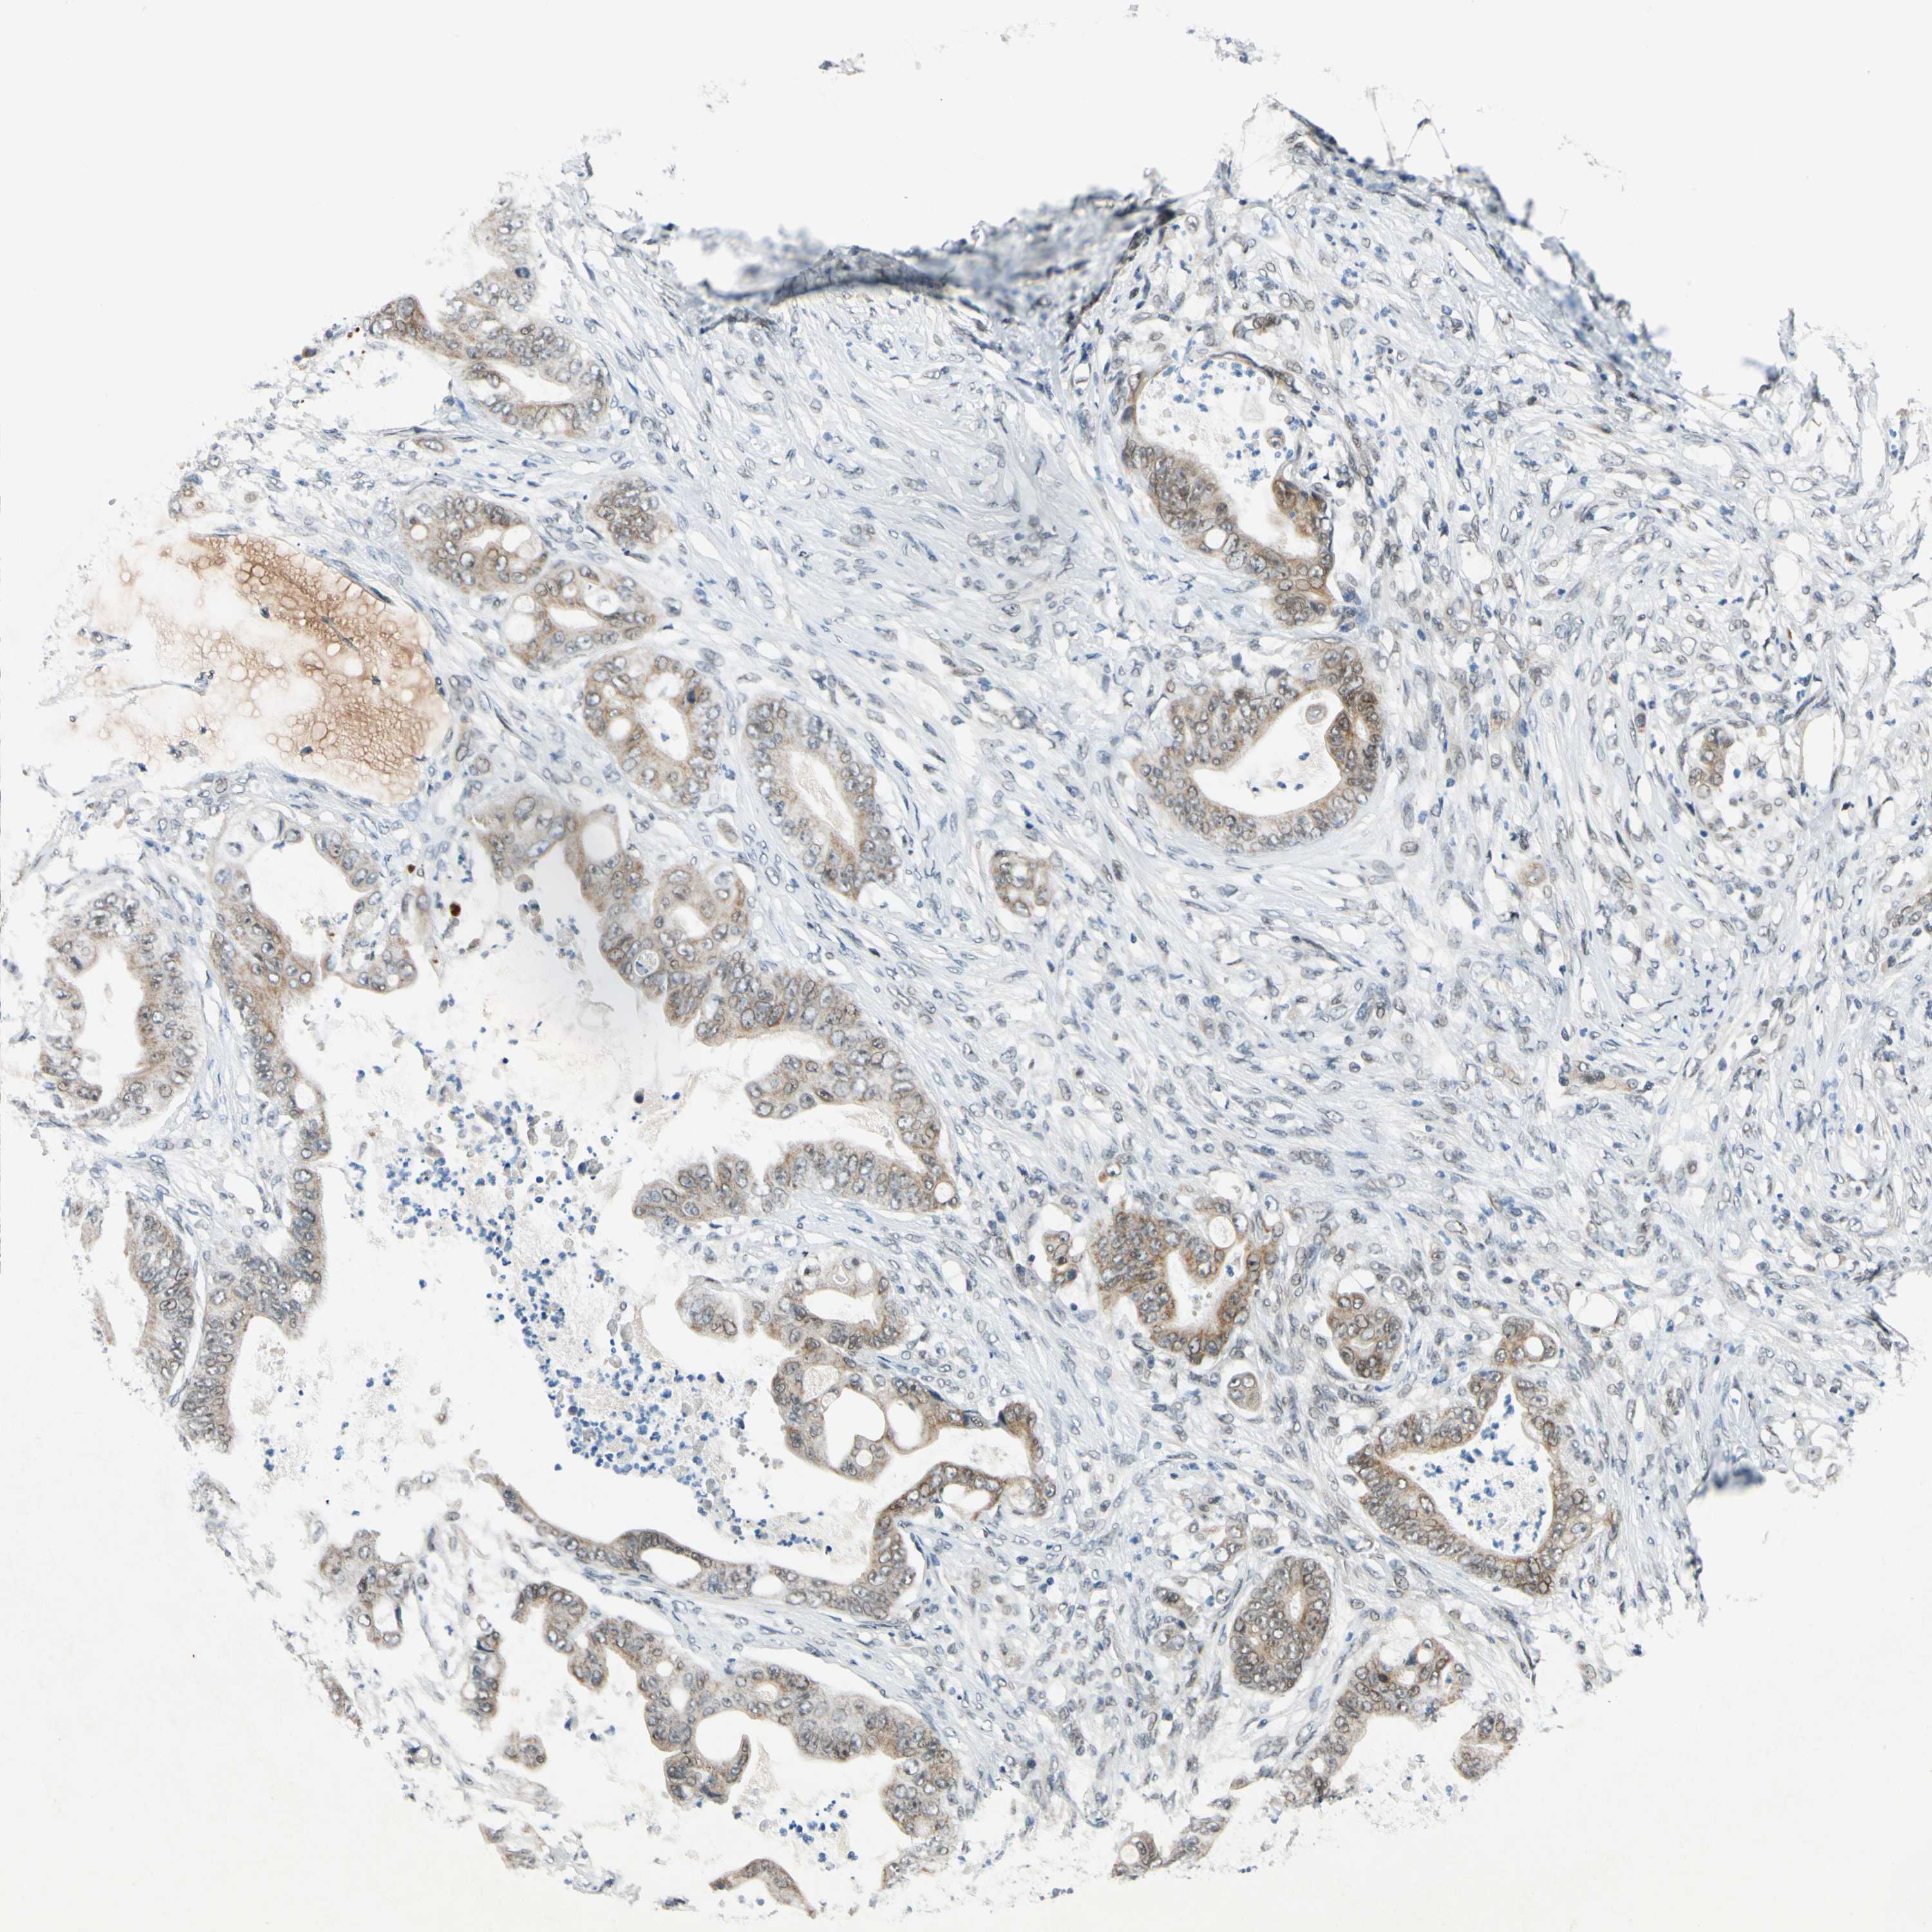

STOMACH CANCER - Protein expressioni

A mouse-over function shows sample information and annotation data. Click on an image to view it in a full screen mode. Samples can be filtered based on level of antibody staining by selecting one or several of the following categories: high, medium, low and not detected. The assay and annotation is described here.

Note that samples used for immunohistochemistry by the Human Protein Atlas do not correspond to samples in the TCGA dataset.

Antibody stainingi

Antibody staining in the annotated cell types in the current human tissue is reported as not detected, low, medium, or high, based on conventional immunohistochemistry profiling in selected tissues. This score is based on the combination of the staining intensity and fraction of stained cells.

Each image is clickable and will lead to virtual microscopy that enables deeper exploration of all samples and also displays staining intensity scores, fraction scores and subcellular localization as well as patient and tissue information for each sample.

Antibody HPA006800

Antibody HPA008781

Staining

High

Medium

Low

Not detected

Intensity

Strong

Moderate

Weak

Negative

Quantity

>75%

75%-25%

<25%

None

Location

Nuclear

Cytoplasmic/membranous

Cytoplasmic/membranous,nuclear

Adenocarcinoma, NOS